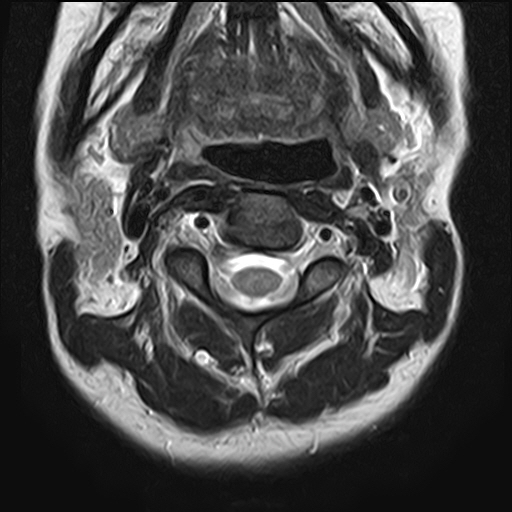

• 1번 째 사진

• 2번 째 사진

• 3번 째 사진

• 4번 째 사진

• 5번 째 사진